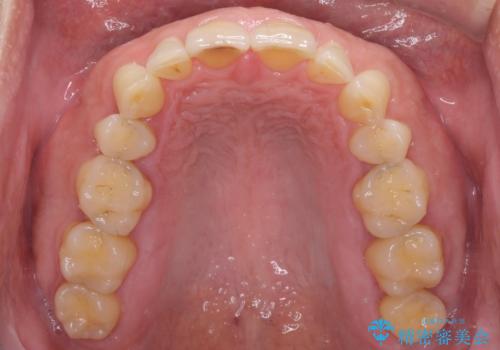

- 前歯の目立つ隙間を気にして来院された患者様です。

高校生の頃に矯正治療を行ったものの、強い咬合力により上顎が拡大され、正中に隙間ができてしまいました。

通常では歯の周囲全体を削った上でクラウンを装着することが多いのですが、咬合力が非常に強く、クラウンではセラミックが欠けてしまう可能性が考えられたため、咬合を変えることとのないラミネートベニアにて治療を行うこととしました。